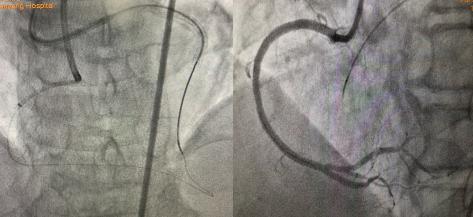

2021年9月26日秋雨綿綿,患者雙側(cè)指引導(dǎo)管造影示:如圖1。

圖1:右冠近段閉塞,前降支-穿膈支-后降支側(cè)枝循環(huán)形成CCI級(jí),J-CTO評(píng)分4分-高難度CTO病變。

圖2 AGT技術(shù)—正向Guidezilla延長(zhǎng)導(dǎo)管成功迎接逆向微導(dǎo)管